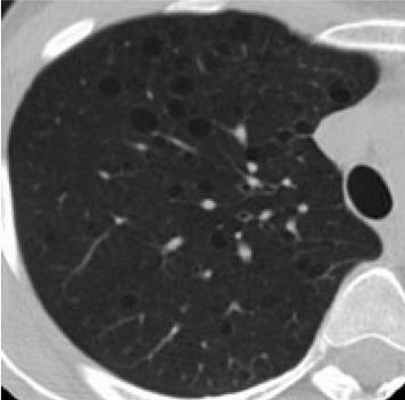

Фрагмент КТ: множественные кистозные изменения - лимфангиомиоматоз легких

Лимфангиолейомиоматоз легких. Легкие вовлекаются в патологический процесс после 30 лет. Первые клинические симптомы - дыхательная недостаточность и рецидивирующий пневмоторакс.

Легочные изменения: исследования выявили кистозные изменения легочной ткани у 40% женщин с ТС.